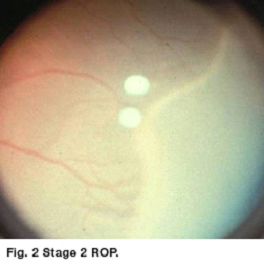

ROP is described by its location in the eye (the zone), by the severity of the disease (the stage) and by the appearance of the retinal vessels (plus disease). The first stage of ROP is a demarcation line that separates normal from premature retina. Stage 2 is a ridge which had height and width. Stage 3 is growth of fragile new abnormal blood vessels. As ROP progresses the blood vessels may engorge and become tortuous (plus disease) [See figures 2 and 3].